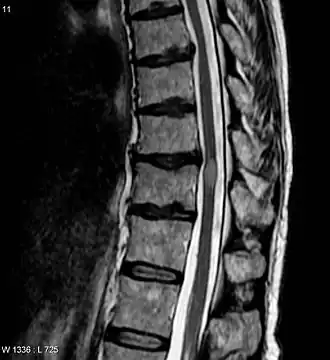

| Imagem por ressonância magnética (IRM) mostrando uma lesão de mielite transversa (exame realizado 3 meses após a recuperação do paciente). | |